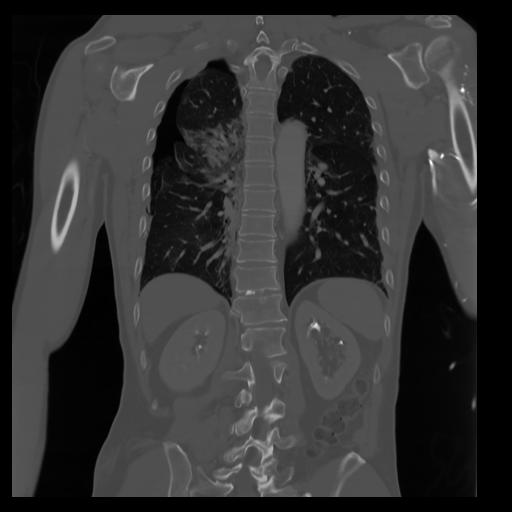

29 CUERPO,CE,Coronal,3.000,CUERPO,Coronal,